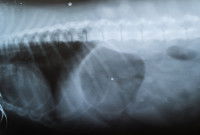

En soi, diagnostiquer un souffle au coeur chez un chien n'est pas très difficile : une simple écoute avec un stéthoscope permet de le faire, par exemple lors d'une visite de routine chez le vétérinaire.

Là où les choses se compliquent, c'est qu'il faut ensuite remonter jusqu'à la cause sous-jacente, et évaluer la gravité de l'atteinte cardiaque. Cela passe une étude plus précise du souffle constaté, ainsi que par un ou plusieurs autres examens.

En plus de l'étude précise du souffle cardiaque en lui-même, divers examens complémentaires peuvent être utiles pour aider à déterminer le problème qui en est à l'origine.

On peut citer par exemple :